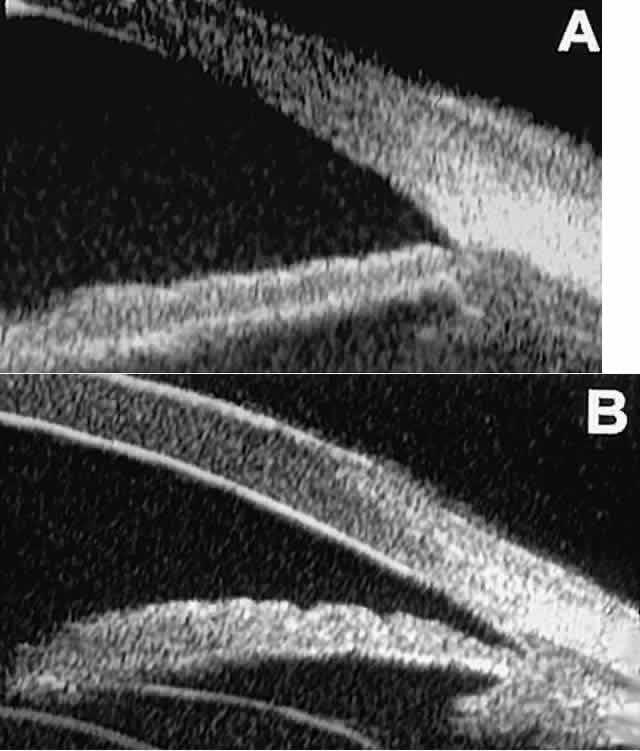

In eyes with a narrow angle, UBM shows the extent of angle closure, reveals

the depth of the anterior and posterior chambers, and identifies

pathologic processes pushing the lens and iris forward (Fig. 11).2–4,8 UBM has been able to differentiate between primary angle closure (i.e., cases of angle closure without additional pathology responsible for the

anterior lens-iris displacement [see Fig. 11A] and secondary angle closure due to processes such as lens swelling

and dislocation (see Fig. 11B), massive hemorrhagic retinal detachment pushing the lens and iris anteriorly (see Fig. 11C), and multiple neuroepithelial cysts of the iridociliary sulcus (see Fig. 11D).  Fig. 11. Angle configuration in eyes with angle-closure glaucoma. A. Primary angle-closure glaucoma with anterior displacement of lens and

iris. B. Angle closure secondary to swollen, cataractous lens (phakomorphic angle

closure). C. Angle closure secondary to massive hemorrhagic retinal detachment; the

subretinal blood is evident in the lower right corner of the photograph. D. Angle closure secondary to multiple peripheral iris cysts. Fig. 11. Angle configuration in eyes with angle-closure glaucoma. A. Primary angle-closure glaucoma with anterior displacement of lens and

iris. B. Angle closure secondary to swollen, cataractous lens (phakomorphic angle

closure). C. Angle closure secondary to massive hemorrhagic retinal detachment; the

subretinal blood is evident in the lower right corner of the photograph. D. Angle closure secondary to multiple peripheral iris cysts.